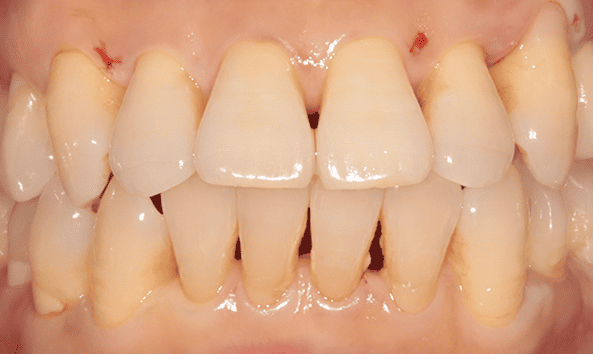

붓고 피나는 잇몸을 건강하게 잇몸치료로 회복하세요!

건강한 치아는 건강한 잇몸이 있기에 존재합니다. 성인의 절반 이상이 잇몸 질환을 모르고 방치하고 있습니다. 잇몸질환, 꾸준한 관리를 통해 개선해드리겠습니다.

잇몸 질환 치료에는 비수술적 치료와 수술적 치료 방법이 있습니다.

건강한 잇몸

치주낭 길이 3mm 이하

스케일링 치료

치은염

치주낭 길이 3~5mm 이하

치근활택술 치료

초기 치주염

치주낭 길이 5~7mm 이하

치주소파술 치료

중기 치주염

치주낭 길이 7mm 이상

치주 수술